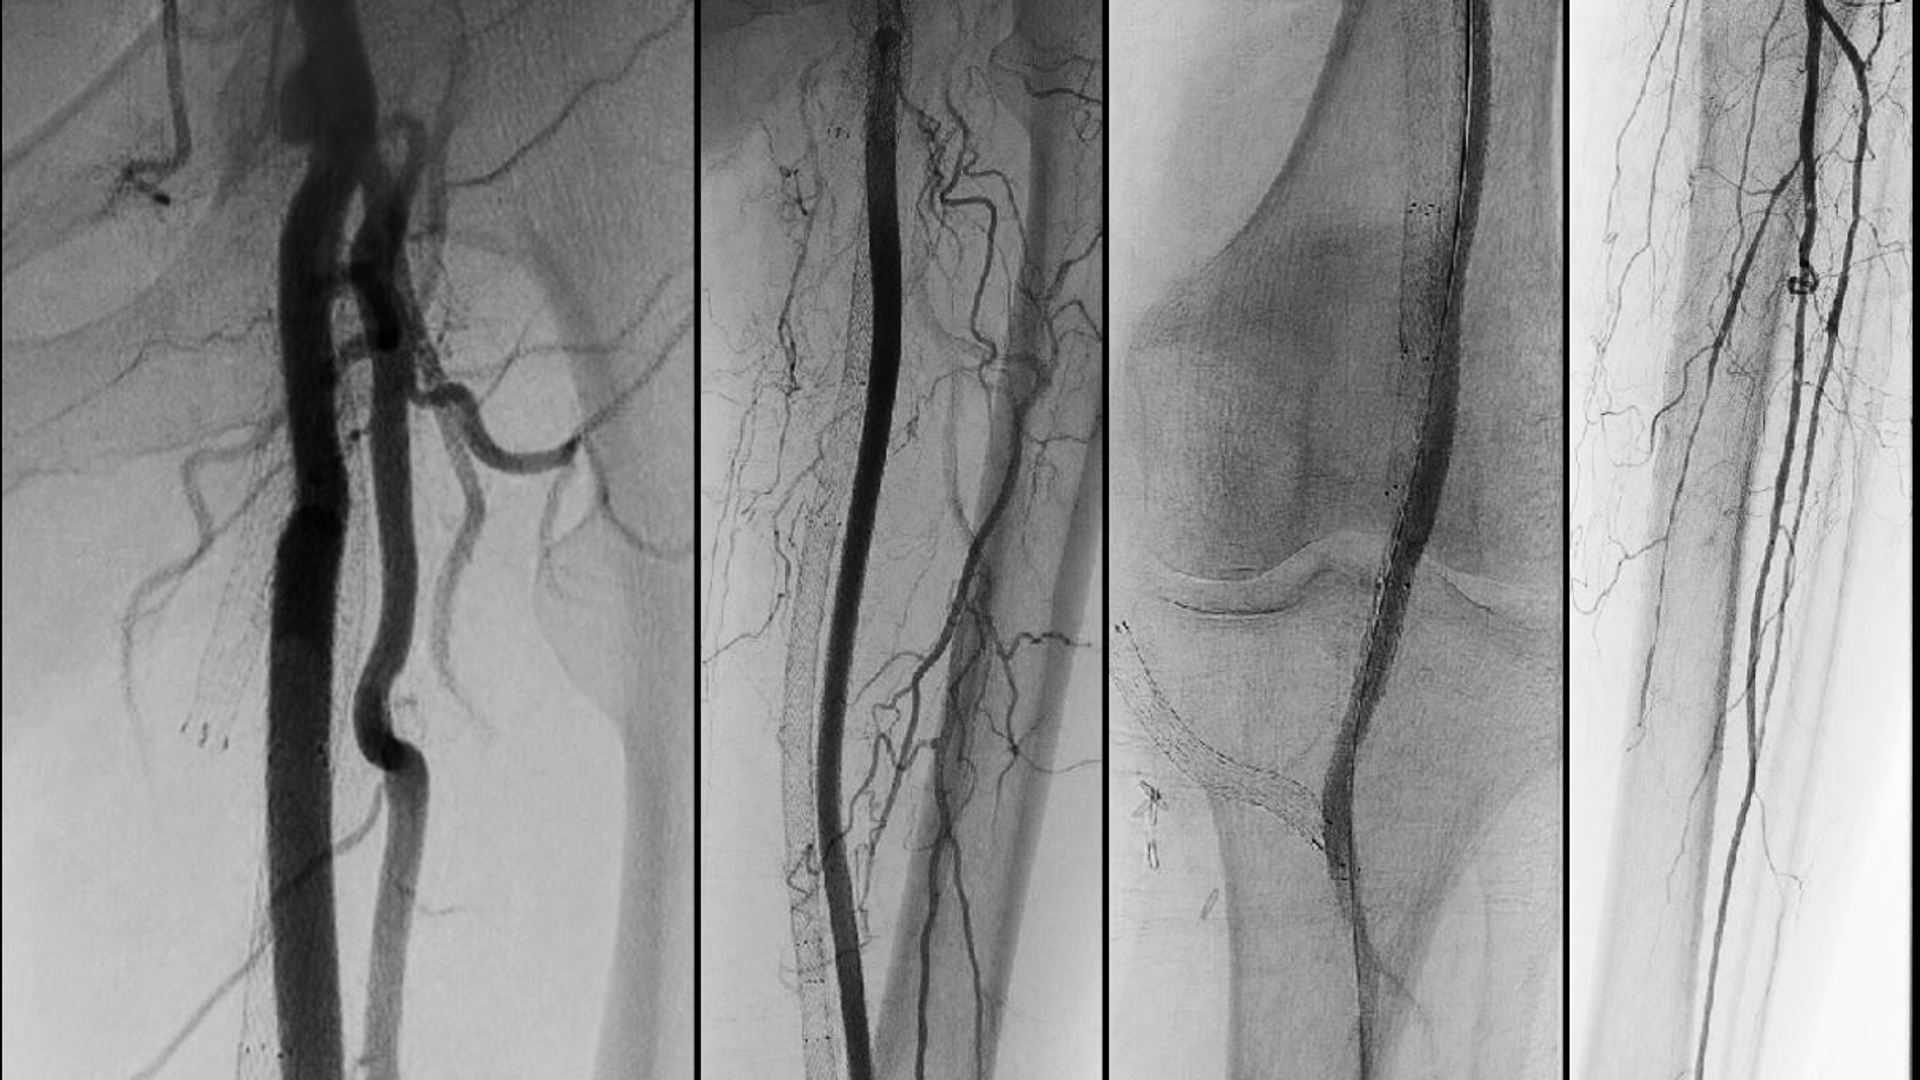

Two scans demonstrate the reduction in blood flow to the lower leg caused by a long clot in the femoral artery shown in detail in the left image

Figure 1: Preintervention angiogram demonstrates flush occlusion of previously revascularized SFA as well as surgical bypasses. Reconstitution of the popliteal artery at the knee seen with thready 2 vessel tibial runoff.